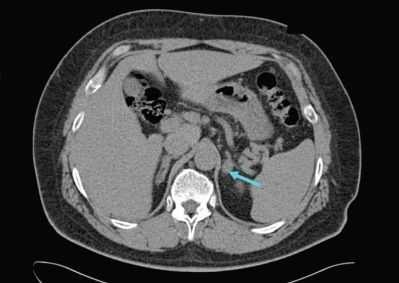

По результатам компьютерной томографии выявлено образование левого надпочечника с чёткими контурами овальной формы размерами 19*27*18 мм, увеличение регионарных лимфатических узлов поджелудочной железы и печени.

УЗИ органов брюшной полости: диффузные изменения печени и поджелудочной железы, признаки неалкогольной дистрофии печени. Гиперплазия/образование левого надпочечника. Правый надпочечник — без особенностей.